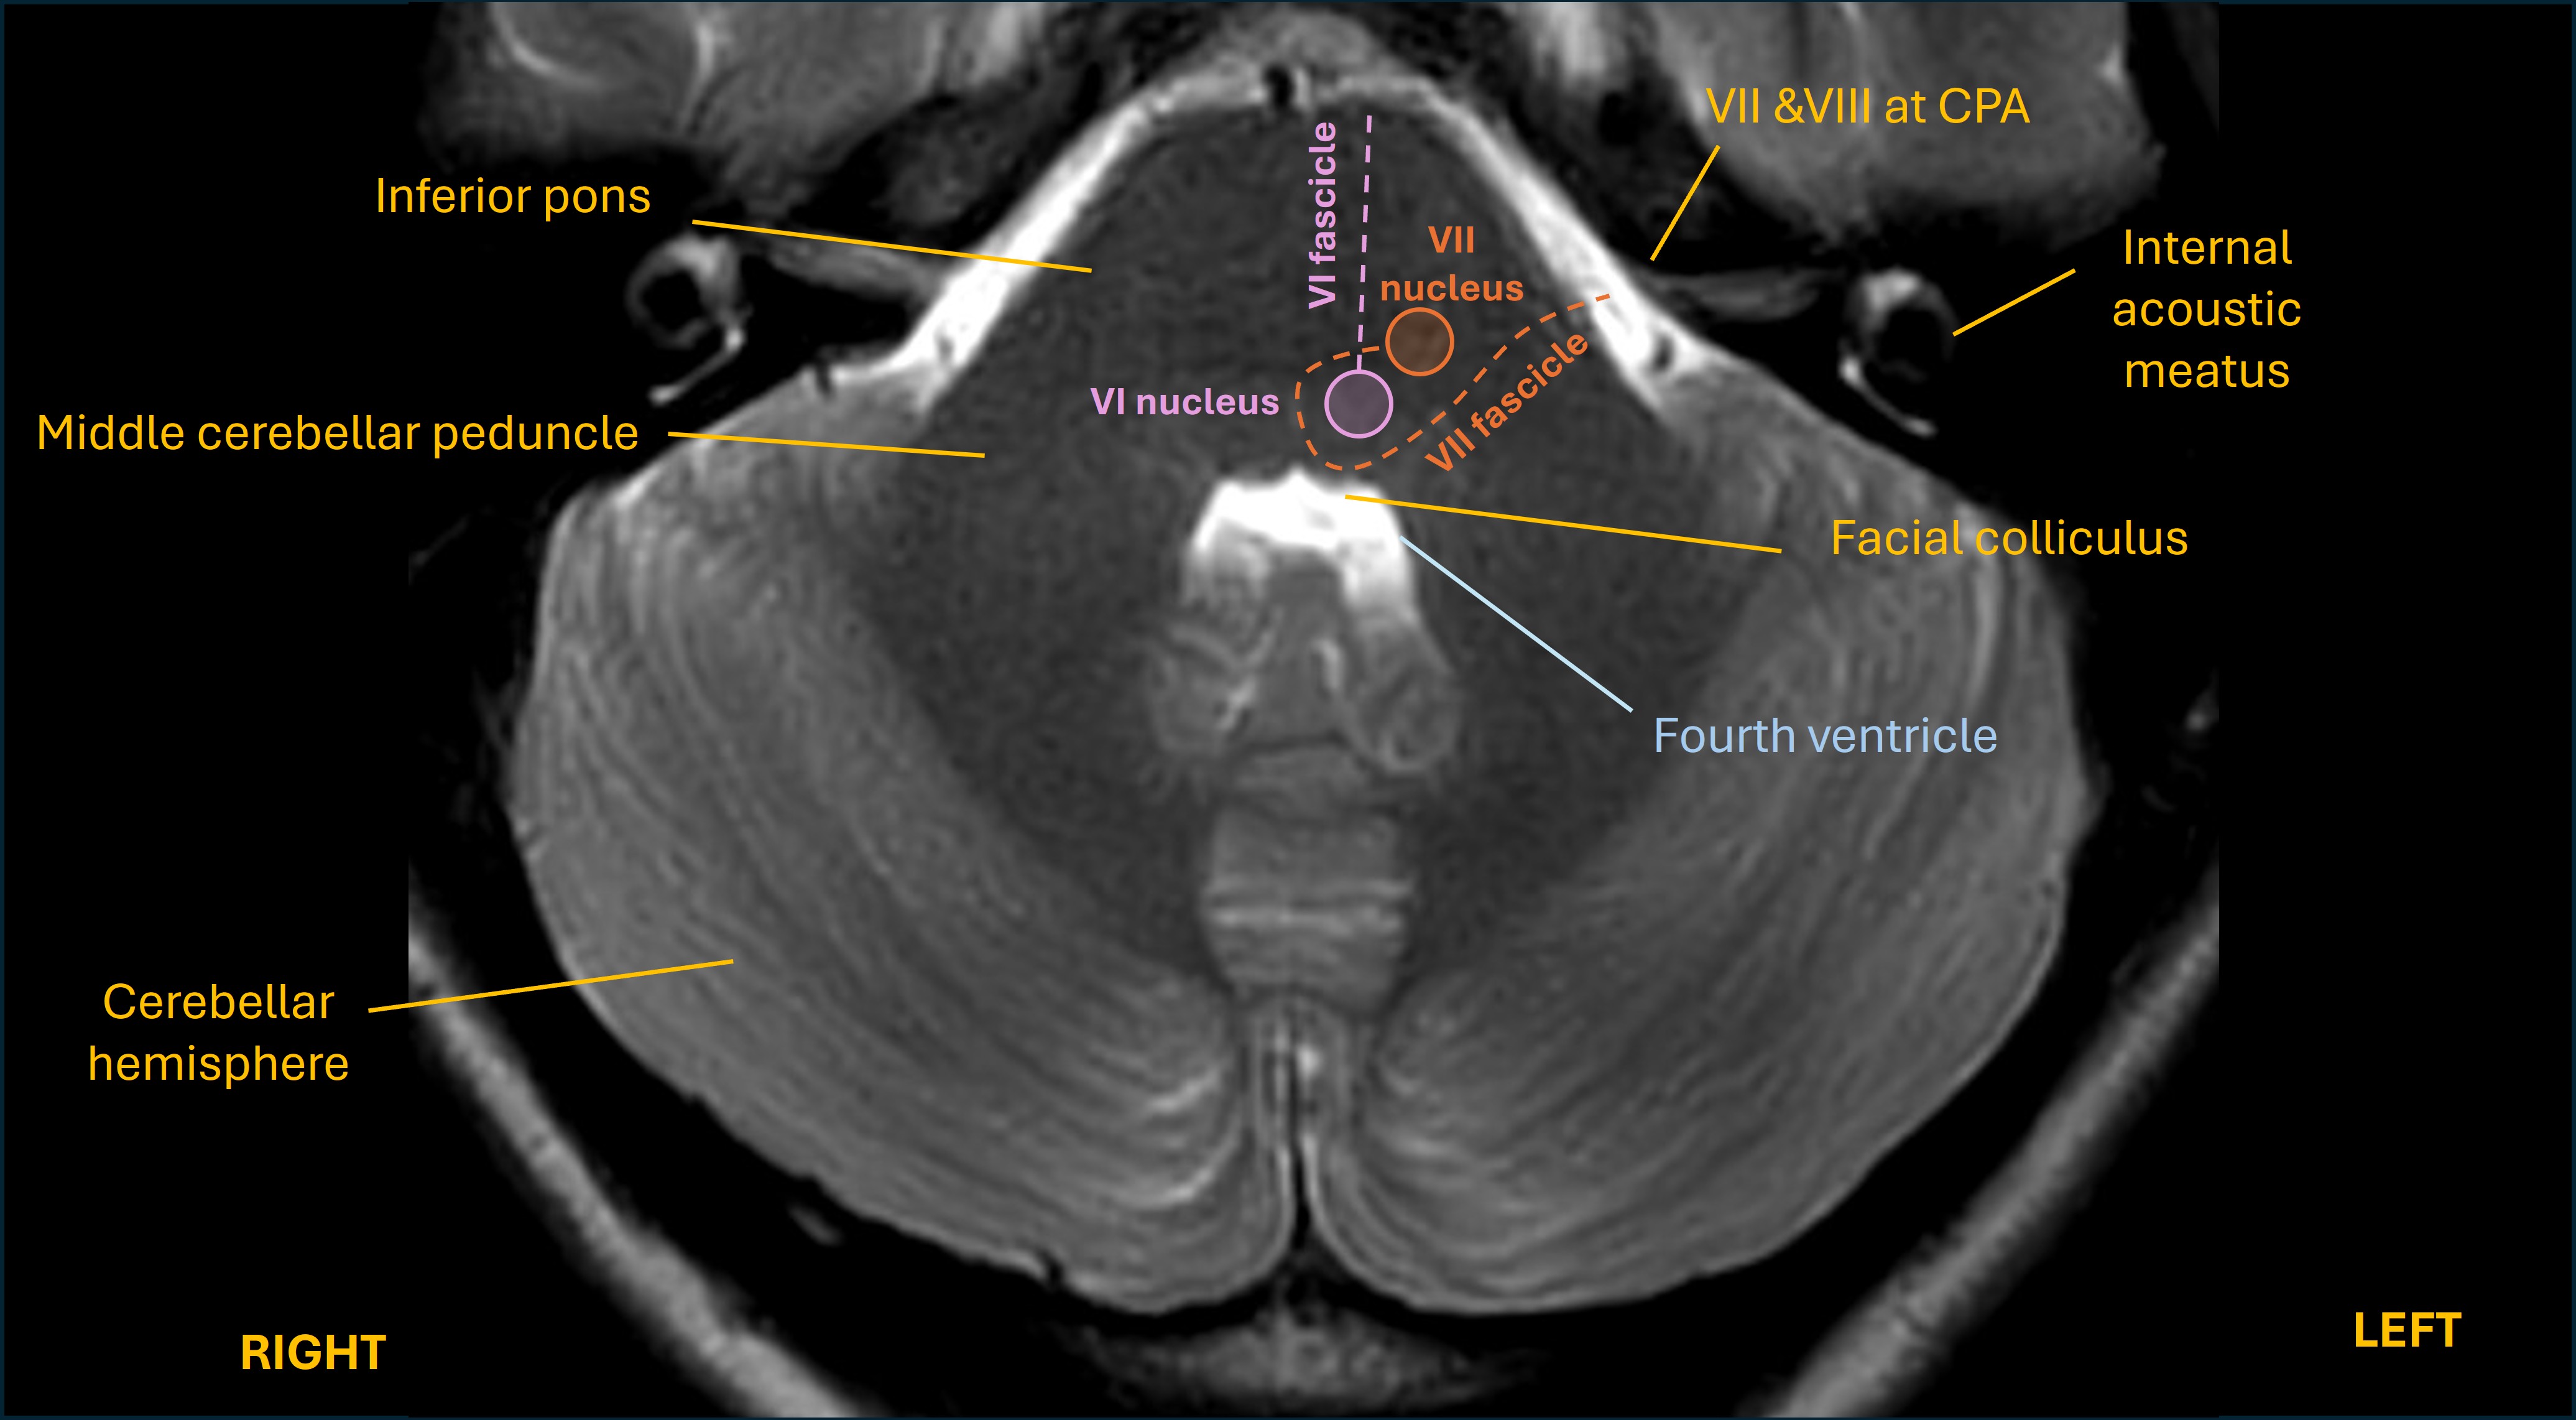

If other structures are then affected we may see additional combinations. One is when the facial nerve fibres are affected - they travel backwards and loop around the VI nucleus at the facial colliculus (which looks like a mound in the floor of the 4th ventricle).

Facial colliculus

A lesion also affecting them produces lower motor neuron VII palsy on the same side as the affected PPRF. This combination - a 7th nerve palsy - is 'added' to one-and-a-half syndrome to make eight-and-a-half syndrome.

Another entity, facial colliclus syndrome, is a reference to the combinations of facial weakness and any of VI palsy, INO or conjugate gaze paralysis that can occur due to lesions here. Sometimes ataxia also arises as the middle cerebellar peduncle is involved.